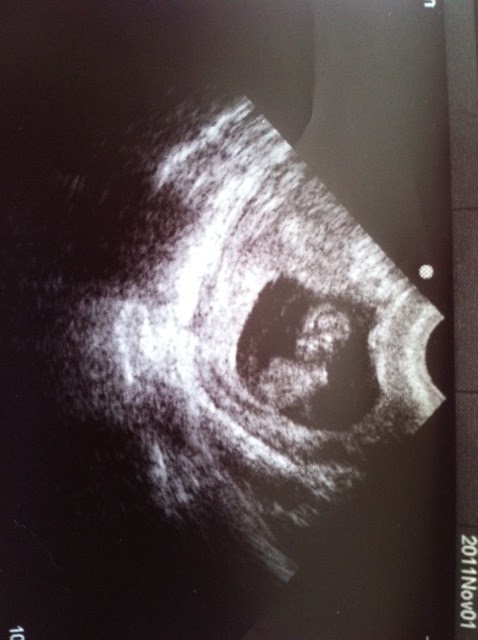

I've been bad, I haven't been posting every weekend. But the truth was that there wasn't much to tell except that we got our boardgames and were eagerly board gaming every weekend with people. An then I starting feeling crumby all the time and it turns out I'm pregnant!

See there's the spud! Blogger seems to think this photo is sideways and I can't fix it. It's a very active little thing - always moving around, I guess it's got a good heart beat and looks normal. I'm still due on May 26th so we'll just cross our fingers that the morning sickness ends soon so Ian can eat garlic again. We've been doing surprisingly well with getting baby things acquired - We had a crib donated to us from some wonderful sergeants. We've also got a baby carrier, bathtub, some clothes, an anti roll over device, and play doohicky thing. So far so good. Evertime people give things to us I'm like - What is that? How do you use it? It's really pretty funny how little I know about any of this.